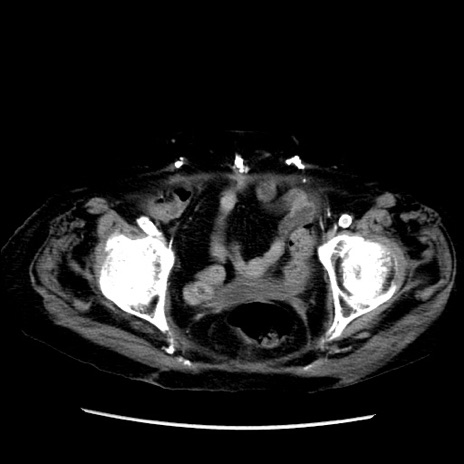

症例14(横断像)

【症例】 90歳代女性

【主訴】 腹痛・嘔吐

【現病歴】今朝から左側腹部痛を認めた。 経過観察していたが、嘔吐を認めたため来院。

【既往歴】 子宮癌術後

【身体所見】 意識清明、BP 127/54mmHg、P 98bpm Sp02 95%(RA)、BT 35.8°C、腹部平坦・軟腸ぜん動音聴取良好、右下腹部圧痛(+) 反跳痛なし

【データ】WBC 9800、CRP 0.46